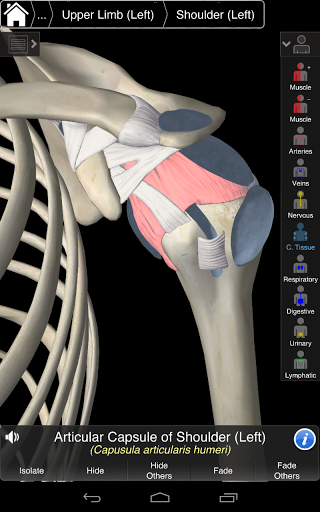

Основна Анатомія 3 чутлива, візуально приголомшлива і легка. Додаток повністю 3D, що означає, що ви можете переглядати будь-яку анатомічну структуру окремо, а також з будь-якого кута.

PREMIUM INTERFACE DESIGN

Основна Анатомія 3 розроблена з урахуванням користувача - сам орган стає інтерфейсом. На відміну від інших 3D-додатків, які покладаються на попередньо визначені анатомічні механізми та регіональні розділи для керівництва користувача, 3D4Medical's Essential Anatomy 3 дозволяє знайти те, що ви шукаєте, без ускладнень.

---- Нова 3D-технологія за допомогою останнього графічного двигуна 3D4Medical

---- Більше 4000 дуже детальних анатомічних структур